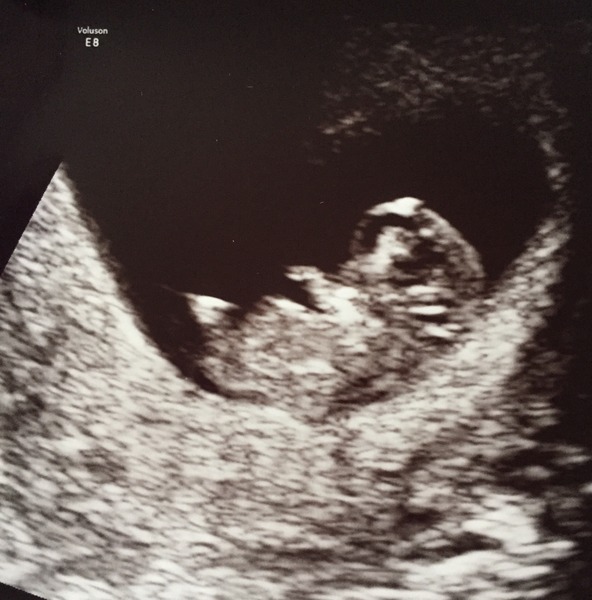

I had an early scan this weekend and happy to say all looked good and we heard a nice strong heartbeat which was lovely. Dates changed slightly making me 9+6 today but no doubt that will change again at my 12 week scan.

I'm going to attempt to post a photo...

FussyHendricks · 01/09/2015 08:21

Here goes...